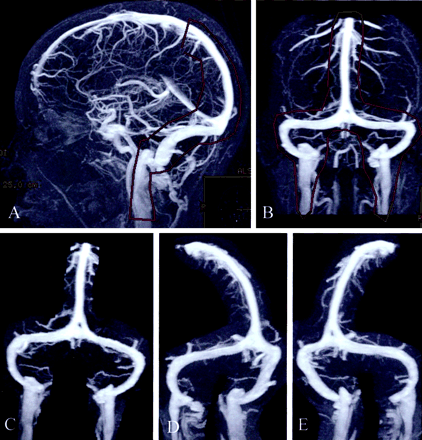

图1所示。Auto-triggered elliptic-centric-ordered控制病人的三维先生gadolinium-enhanced造影术。(一)横向和(B)前后的最大强度投影(MIPs)显示轮廓用来创建序列的分段MIPs获得每个控制和颅内高压症病人。(汉英)前后的左前斜(老挝),右前斜(RAO)分段MIPs。这三个选择拍摄的图像90张图片,电影圈的读者了。